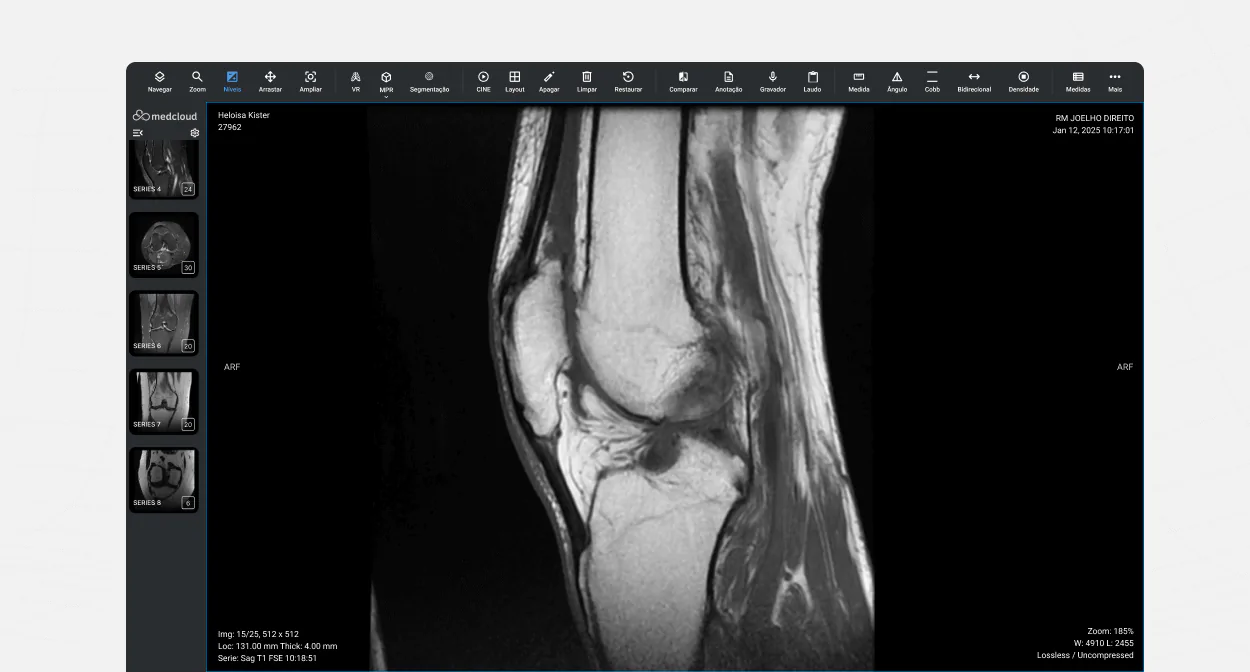

O viewer DICOM da Medcloud

É comum no mercado que o viewer DICOM seja oferecido separadamente do PACS, o que obriga instituições a contratar softwares diferentes e lidar com integrações. Por isso que a Medcloud se destaca ao oferecer um sistema completo: PACS e visualizador DICOM integrados em uma única plataforma, garantindo praticidade, segurança e eficiência sem necessidade de ferramentas adicionais.